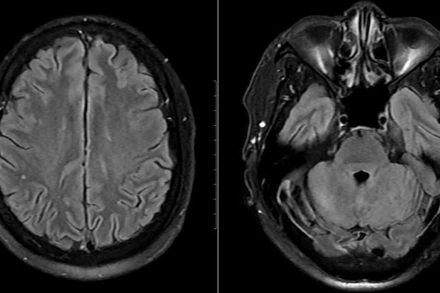

[Video] Vỡ mạch máu và tắc nghẽn: Hai nguyên nhân chính gây đột quỵ

Đột quỵ là tình trạng gián đoạn dòng máu đến não, có thể do tắc nghẽn (đột quỵ thiếu máu cục bộ) hoặc vỡ mạch máu (đột quỵ xuất huyết). Đột quỵ thiếu máu cục bộ gồm tắc mạch và huyết khối. Đột quỵ xuất huyết não nguy hiểm, thường liên quan đến huyết áp cao và có tỷ lệ tử vong cao.